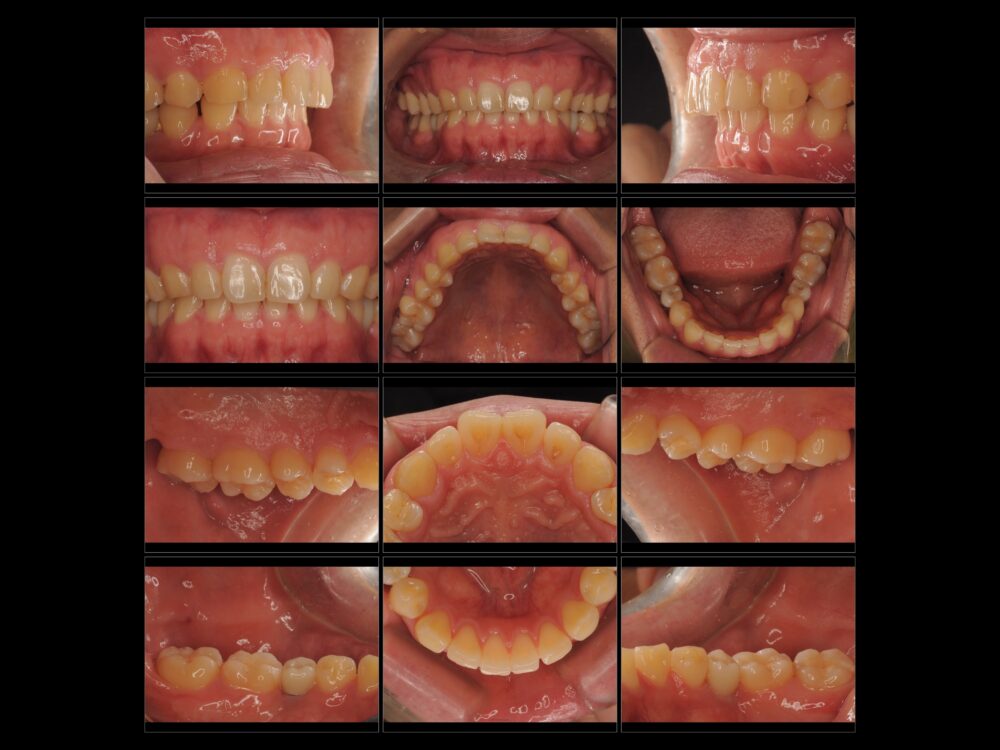

27才、男性です。

家族から「歯ぎしり」がひどいと指摘されたことが心配でお越しになりました。自分では10代後半に左下の奥歯(乳歯)が抜けてしまい、そのままにしていることで咬み合わせが悪くなったことが「歯ぎしり」の原因ではないか…と思っているとのことでした。

両側とも下の5番目の永久歯が生まれつきありません(先天的欠如歯)。

本人は乳歯しかないところがあることは知っていたようで、今回と同様の相談を1年前に他の歯科医院でもしたところ、矯正治療とインプラント治療が必要と言われたものの、治療には至らなかったそうです。